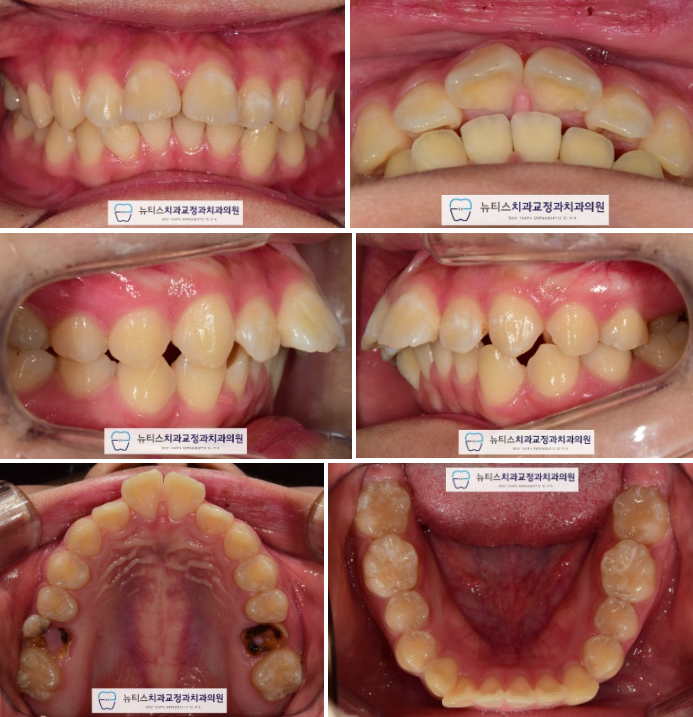

ÃÊÁø »çÁøÀÔ´Ï´Ù.

µ¹ÃâµÈ ¾Õ´Ï¿Í »ß¶Ô¾îÁø Ä¡¾Æ¸¦ º¸ÀÔ´Ï´Ù.

»ó¾Ç Á¦ 1 ´ë±¸Ä¡´Â À̰¡ ½â¾î¼

¸Ó¸®ºÎºÐÀÌ ¾ó¸¶³²Áö ¾Ê¾Ò½À´Ï´Ù.

Æ¢¾î³ª¿Â ¾Õ´Ï

Ʋ¾îÁø Ä¡¾Æ

¸ÂÁö ¾Ê´Â ±³ÇÕ

»Ì¾Æ¾ßµÇ´Â Ä¡¾Æ

µîÀ» °í·ÁÇÏ¿©

À§¿¡´Â ½âÀº Ä¡¾Æ 2°³¸¦,

¾Æ·¡ÂÊ¿¡´Â ÀÛÀº ¾î±Ý´Ï 2°³¸¦ ¹ßÄ¡Çϱâ·Î ÇÏ¿´½À´Ï´Ù.

±³Á¤ ¿Ï·á ÈÄ »çÁøÀÔ´Ï´Ù.

°¡Áö·±ÇÑ Ä¡¿À» º¸À̸ç

±³ÇÕ°ü°è°¡ Åé´Ï ¹°¸®µíÀÌ Çü¼ºµÇ¾ú½À´Ï´Ù.

ÀÓÇöõÆ® ´ë½Å À̸¦ »ÌÀº °ø°£À» ÀÌ¿ëÇÏ¿©

µ¹ÃâµÈ ¾Õ´Ï¿Í »ß¶ÔÇÑ Ä¡¾Æ¸¦ °¡Áö·±ÇÏ°Ô ¸¸µé¾ú½À´Ï´Ù.